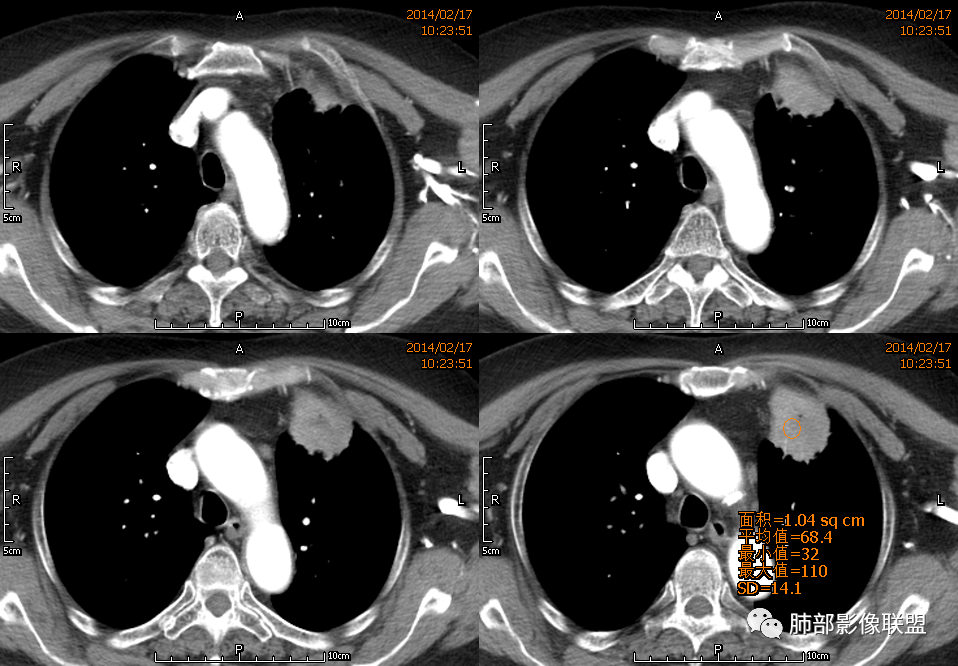

薏米: 老年女性,急性起病,咳嗽,咳痰,咯血,白细胞低,胸部CT提示左肺上叶可见一团块样密度增高影,边缘平直,部分略有膨隆,内可见支气管进入后截断,小的空洞,血管造影,坏死,明显强化,周边可见少许索条,考虑炎性病变,肺脓肿可能。鉴别结核,隐球菌。

红星: 老年女性,咳嗽咳痰10天,痰中带血4天。左肺上叶前段胸膜下肿块影,沿支气管方向走行以膨胀生长为主,局部有收缩改变,支气管血管绝断,中间有小片状的坏死及小的空洞影,增强扫描病灶明显的强化,病灶周围网格状的小叶间隔增厚。拟左肺上叶前段浸润型腺癌并癌性淋巴管炎。鉴别诊断结核肉芽肿。

傅昌瑜: 老年女性,咳嗽咳痰10天,痰中带血4天。左肺上叶前段胸膜下肿块影,沿支气管方向走行,膨胀生长为主,局部边缘似有收缩改变,中间有小片状的坏死,支气管进入,增强扫描病灶明显的强化,血管走形较自然(血管漂浮征?),病灶周围网格状的小叶间隔增厚。考虑淋巴瘤可能性大,注意鉴别炎性肉芽肿及肺腺癌。

水晶石头: 患者老年女性,咳嗽咳痰10天,痰中带血4天余。查血常规白细胞低;肿瘤标志物、凝血功能正常;血生化:蛋白低;C反应蛋白、血沉稍升高。胸部CT:左肺上叶前段胸膜下沿气管支气管走形肿块影,长轴与胸膜平行,见分叶、毛刺、支气管截断、空泡征象。增强明显强化,且见血管造影征及病灶内小灶低密度坏死区。左肺上叶尖后段见一结节灶。综合考虑恶性病变可能大,腺癌或淋巴瘤可能。鉴别诊断肺脓肿。

尘缘: 老年女性,咳嗽咳痰10天,痰中带血4天,白细胞及中性粒明显减低,轻度贫血。影像表现:左上叶肿块,边缘膨隆,局部平直,支气管稍扩张,进入后远端堵塞,内见小空洞及不规则坏死区,增强后强化明显,坏死边界较清,并见环状强化区,内部血管走行自然,周围见小叶间隔增厚呈大网格征。初步诊断:慢性炎性伴脓肿形成及肉芽组织增生。鉴别淋巴瘤及腺癌,先抗炎治疗后复查或直接穿刺明确。

毛勤香: 老年女性,左肺上叶胸膜下肿块,部分膨隆部分收缩,边缘毛糙模糊,周围少许索片状影,小叶间隔增粗,支气管进入后截断,增强扫描明显不均匀强化,内低密度区无明显强化,血管走行尚可,首先考虑感染性变并脓肿形成,鉴别淋巴瘤,建议抗炎后复查。

王崇军: 老年女性,咳嗽咳痰10天,痰中带血4天。左肺上叶前段胸膜下 肿块影及段形态密度增高影,沿支气管方向走行,膨胀生长为主,局部有收缩改变,支气管进入并闭塞,中间有小片状的坏死及小的空洞影,空洞漂浮在坏死边缘,增强扫描病灶明显的强化,坏死边界清楚,似乎有轻度强化环,病灶周围网格状的小叶间隔增厚及小结节影,外侧胸膜呈糊墙改变。考虑为肺脓肿,这么大的病灶,竟然没有发烧,白细胞低,CPR轻度升高,均与脓肿不符,所以恶性待排,短期抗炎治疗后复查,病灶没有变化,脓肿就可以排除,恶性基本可以确定。

王武章: 灶内低密度,花环样强化,血管穿行漂浮,邻近胸膜并未广泛增厚也未牵拉但接触面脂肪密度略高且模糊。考虑IMT,鉴别慢性炎症相关的非特异性瘤样病变。

1、坏死区环形强化,指向慢性脓肿。

2、坏死区有血管,基本排除结核。

3、这个卫星灶,更进一步定了大方向,炎性。

※综上所述,看到这四幅图,基本能够准确诊断炎性※

3.病灶密度不均,中央坏死液化并见气泡影,支气管及血管贴边进入,较均匀环形强化(显示多层结构),未见明确壁结节。

3.病灶易坏死液化,环形强化,支气管及血管贴边进入,“火焰”样边缘轮廓,更符合炎性块影的特点。